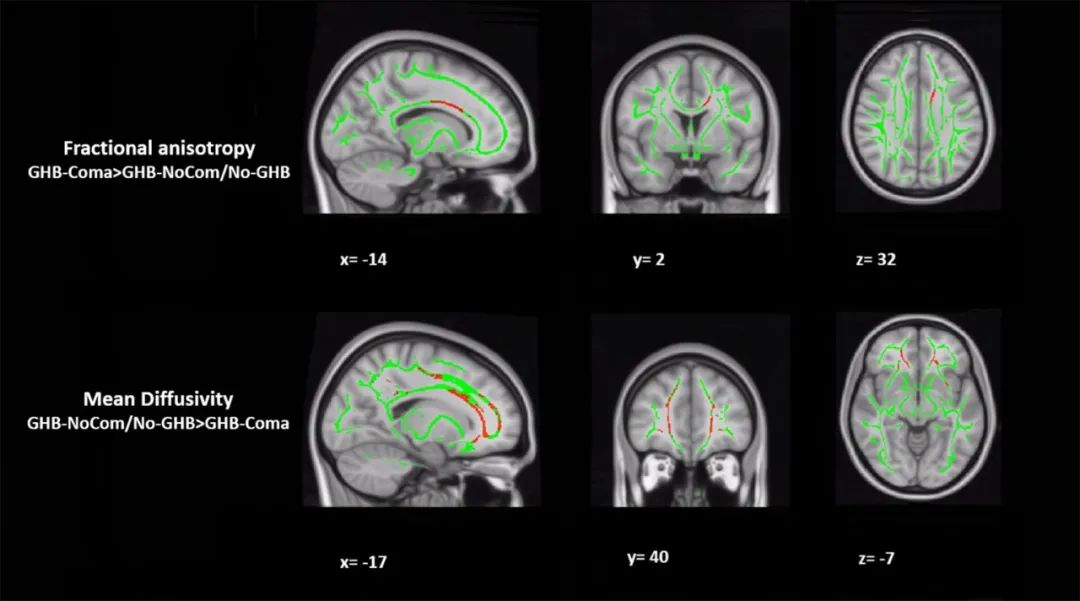

那么,“G水”到底是什么呢?为何让那些坏人屡屡得手呢?这是因为“G水”主要成分是一种有机化合物,名字叫γ-羟基丁酸,简写为GHB,化学式为C4H8O3,分子量为104.1,一种无色无味的液体。

γ-羟基丁酸是一种天然存在的精神活*药性**物,在医学中可用作*醉药麻**品和*眠药安**,其实,γ-羟基丁酸也广泛存在于食物中,例如牛肉,葡萄酒,水果中就有,人在兴奋的时候,大脑也会产生γ-羟基丁酸,发挥神经递质的作用,让人心情非常愉悦。

不论是大脑自动产生的γ-羟基丁酸,还是食物自动产生的羟基丁酸,量都极少,那都不对人体健康造成影响,只有当用量达到0.5~1.5克时,人才会出现上述所说的明显精神反应,任人摆布,这才让坏人钻了空子,有侵犯的想法。

当γ-羟基丁酸用量超过3.5克,人快速失去自觉,呼吸困难,心跳变慢,还会出现抽搐、恶心呕吐的现象,这个时候人就有生命危险,即便后来恢复正常了,也会长时间影响人体健康,对记忆力、表达能力和行动力多少有影响。